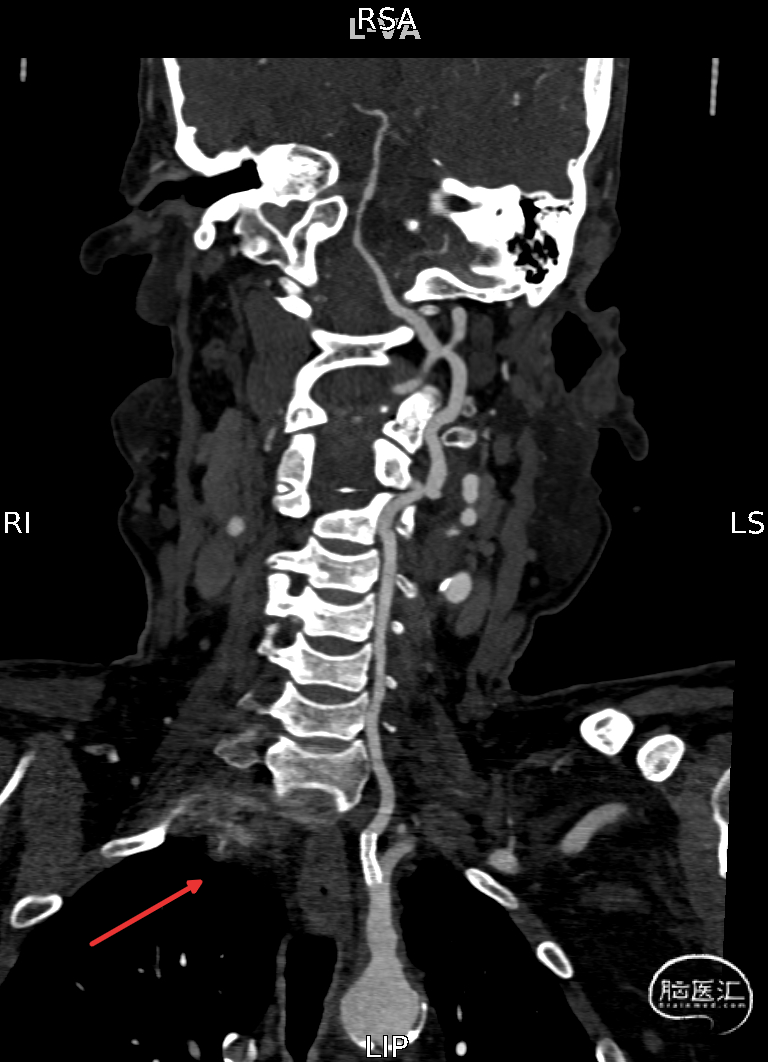

CTA提示:右侧椎动脉纤细,左侧椎动脉V1、V4段纤细。

右侧颈内动脉起始部中度狭窄,未见血流向后循环代偿。

左侧颈内动脉造影提示后交通开放,代偿供应后循环。

左侧椎动脉开口重度狭窄,前向血流缓慢,V4闭塞。

8F Guiding置于左侧锁骨下动脉,泥鳅导丝带中间导管无法成功超选,更换微导丝+球囊。

使用球囊接力技术将Guiding送入左侧椎动脉:

保留微导丝、Guiding回撤到锁骨下,观察椎动脉开口:椎动脉开口无法维持。拟行椎动脉开口支架成形术,选用4mm*15mm Bridge椎动脉雷帕霉素靶向洗脱支架。